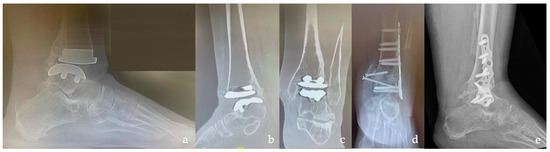

| Type of Plate | Anterior TT | 10 (50%) |

| Anterior TTC | 6 (30%) | |

| Lateral TT | 3 (15%) | |

| Lateral TTC | 1 (5%) | |